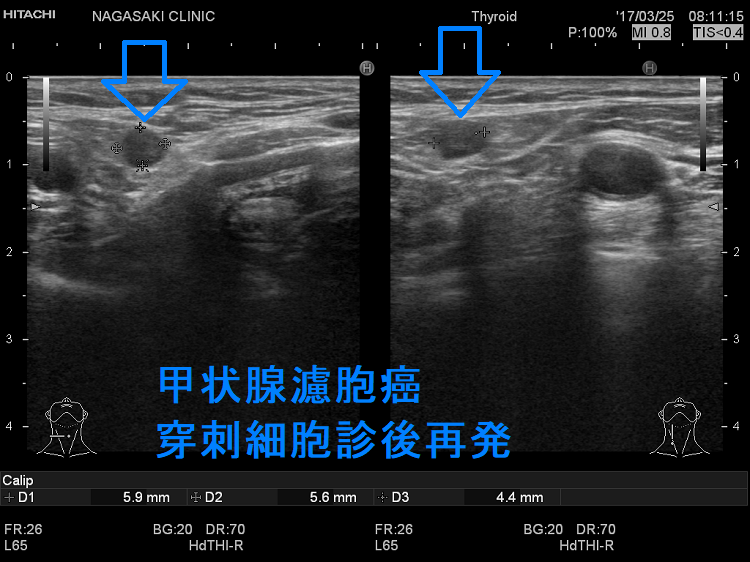

甲状腺穿刺細胞診後再発(穿刺経路再発)

甲状腺濾胞癌 穿刺細胞診後再発 超音波(エコー)画像

甲状腺濾胞癌 甲状腺穿刺細胞診後再発(穿刺経路再発) 超音波(エコー)画像

甲状腺濾胞癌 穿刺細胞診後再発 超音波(エコー)画像 ドプラーモード

甲状腺濾胞癌 甲状腺穿刺細胞診後再発(穿刺経路再発) 超音波(エコー)画像 ドプラーモード

甲状腺濾胞癌穿刺細胞診後の局所再発(甲状腺穿刺細胞診後再発、穿刺経路再発)もあり得ます。穿刺経路に残った濾胞癌細胞の増殖によります。

下の写真は甲状腺濾胞癌摘出後5年して胸鎖乳突筋、肩甲舌骨筋内に発生した甲状腺濾胞癌です。(Surg Today. 2007;37(1):34-7.)

甲状腺濾胞癌 穿刺細胞診後再発